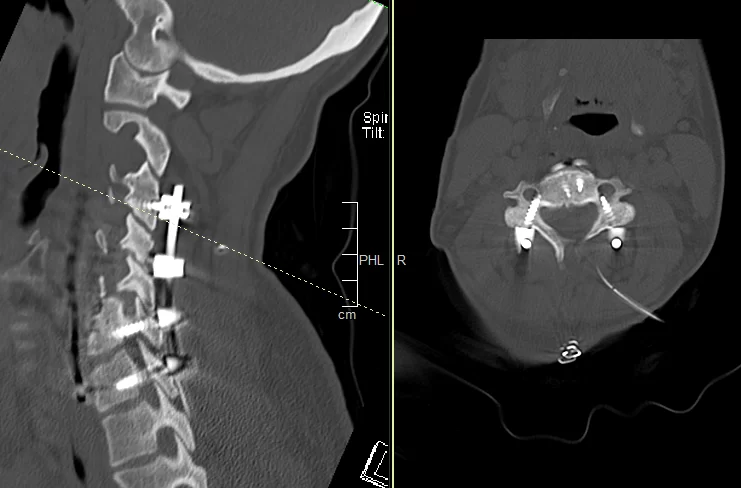

Διενεργήθηκε αρχικά οπίσθια σπονδυλοδεσία με διαυχενικές βίδες Α4, βίδες στα πλάγια ογκώματα Α5 και διαυχενικές βίδες Α7 και Θ1 ενώ έγινε και τρηματεκτομή Α6/7 δεξιά.

Στη συνέχεια, αφαίρεση της πρόσθιας πλάκας, ολοκλήρωση της σωματεκτομής Α5 & Α6, απελευθέρωση του νωτιαίου μυελου, πρόσθια δισκεκτομή Α7/Θ1 και τοποθέτηση πρόσθιας πλάκας Α4-Θ1.

Αρχικά έγινε οπίσθια σπονδυλοδεσία προκειμένω να στηριχθεί ο αυχένας της ασθενούς και να μειωθούν τα άλγη τα οποία οφείλονταν στην “αστάθεια” της αυχενικής μοίρας. Παράλληλα, διενεργήσαμε και οπίσθια τρηματεκτομή ώστε να εξασφαλίσουμε την απελευθέρωση της δεξιάς Α7 ρίζας, η οποία δημιουργούσε πόνο στην ασθενή. Όπως φαίνεται στη μετεγχειρητική αξονική τομογραφία, οι βίδες στους αυχένες του Α4 σπονδύλου τοποθετήθηκαν με ακρίβεια χιλιοστού. Σ’ αυτό, σημαντική ήταν η βοήθεια του διεγχειρητικού νευροπλοηγού σπονδυλικής στήλης με το πιο σύγχρονο σύστημα απεικόνισης (Ο-arm II)

Στη συνέχεια γυρίσαμε την ασθενή σε ύπτια θέση και αφού αφαιρέσαμε την παλαιά πλάκα, αποκαθηλώνοντας τον οισοφάγο, ολοκληρώσαμε τη σωματεκτομή και απελευθερώσαμε τα νευρικά στοιχεία και από μπροστά. Μια και δεν ήταν δυνατή η στήριξη της πλάκας στον Α7, αλλά ούτε και θέλαμε να καταλήξουμε ένα τεράστιο χάσμα, αποφασίσαμε να διατηρήσουμε τον Α7 και να διενεργήσουμε πρόσθια δισκεκτομή Α7/Θ1, καθηλώνοντας τελικά την πλάκα στον Α4, Α7 και Θ1 σπόνδυλο.